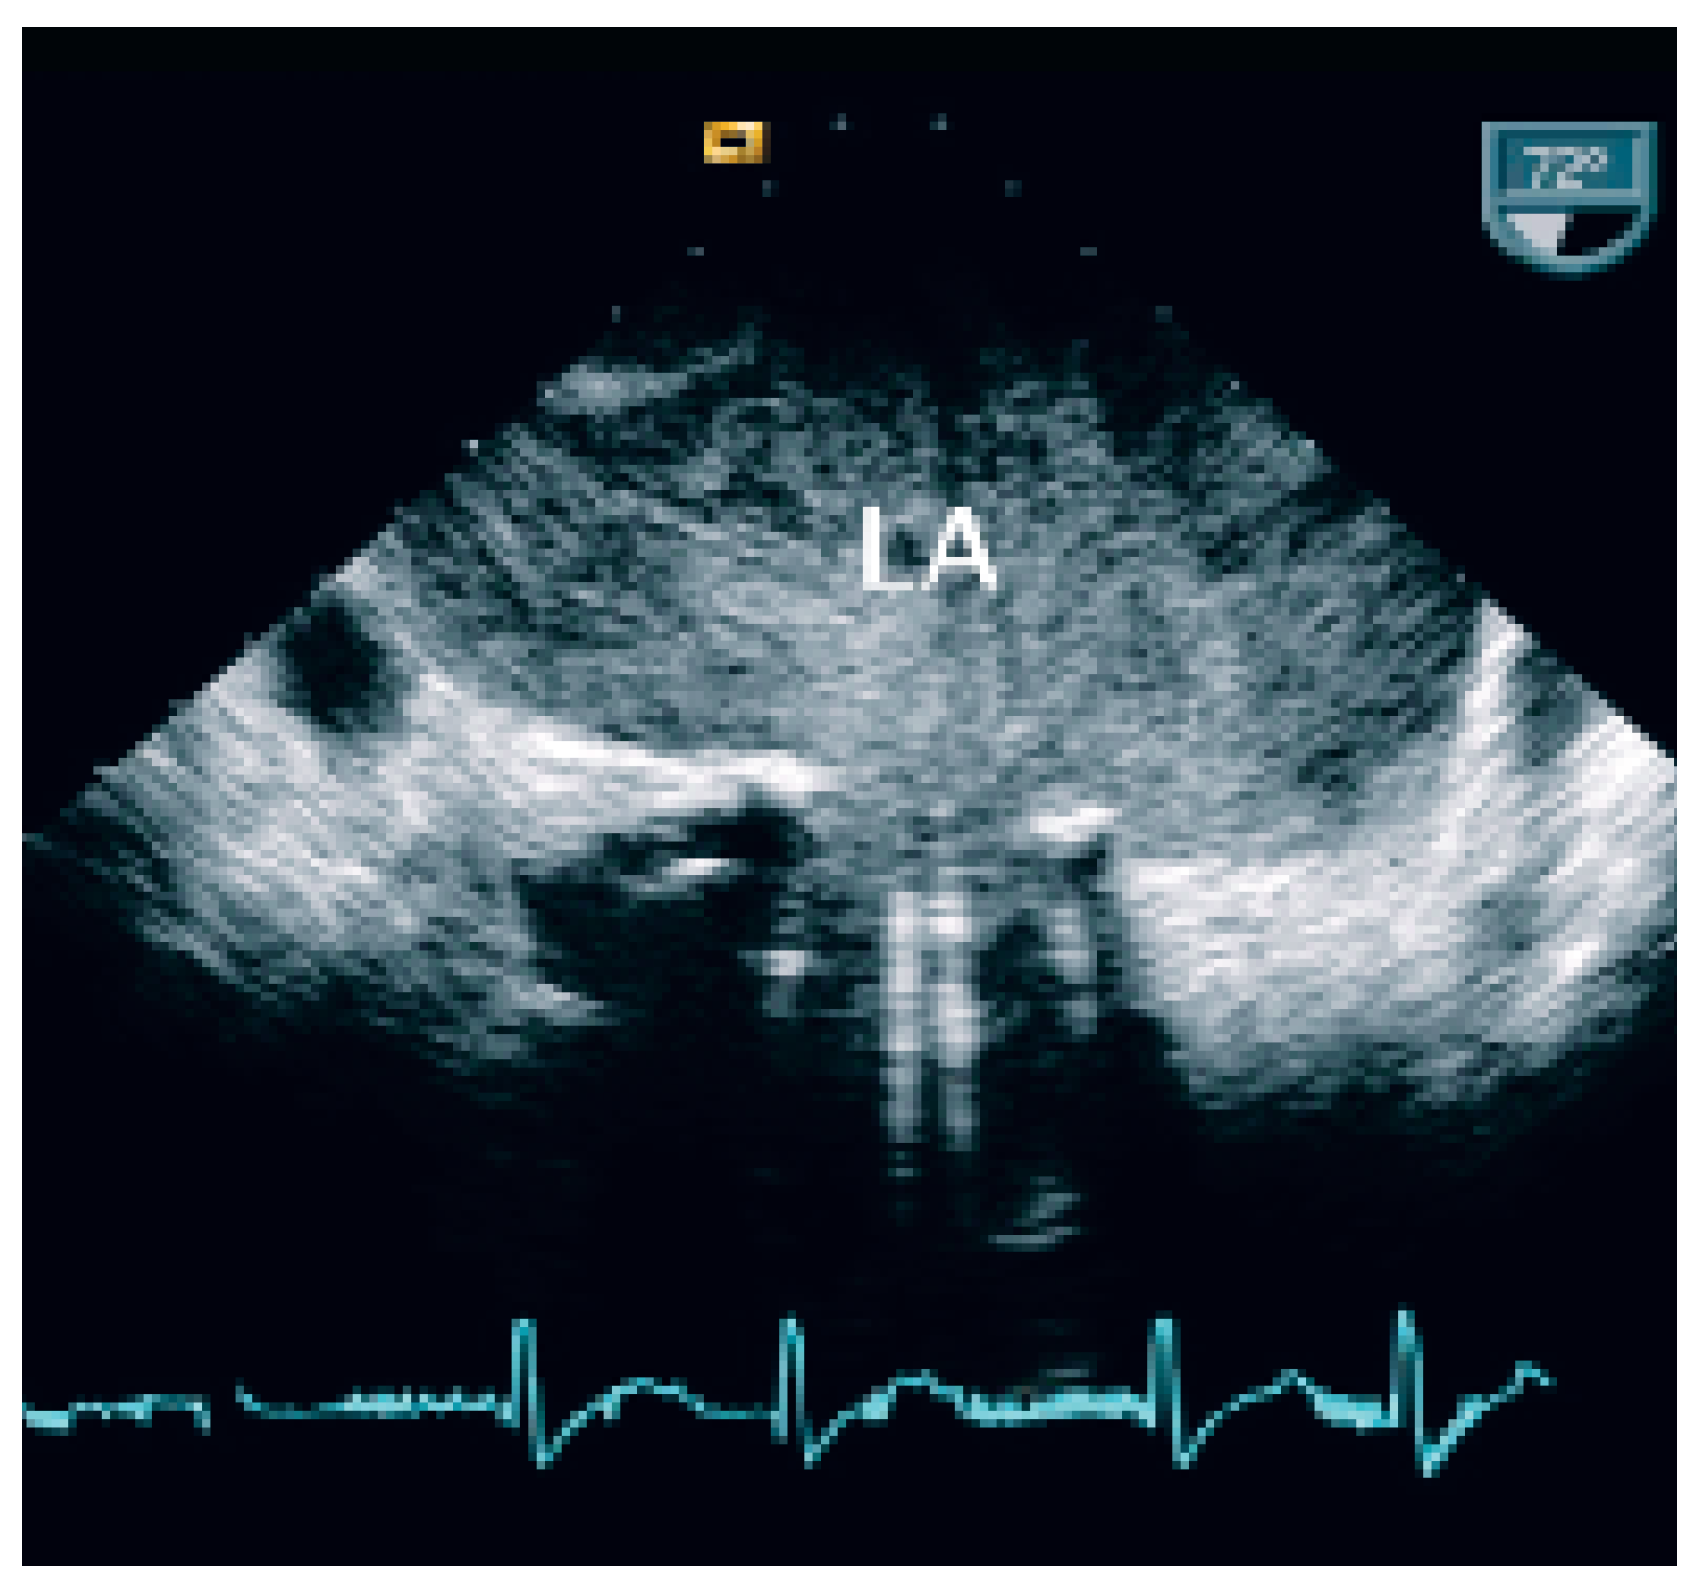

At TEE severe spontaneous echocontrast in the left atrium (Figure 2) and a thrombus (2.7 cm × 3.5 cm) in the left atrial appendix were present (Figure 3). There was no evidence of impairment of the beleaflet mechanical valve (mean transvalvular gradient 4 mm Hg). Anklebrachial pressure index was abnormal (0.5), and duplex ultrasounds showed acute thromboembolic occlusion of right superficial femoral artery.

As cited in Hurst’s memories [1] “… giant left atrium is defined as one that touches the right lateral side of the chest wall. The condition is caused by rheumatic mitral valve disease and atrial fibrillation is always present …”. This case illustrates the pivotal role of echocardiography in defining and quantifying this pathology and the associated thromboembolic risk. TTE and particularly TEE allowed to assess the magnitude of the giant left atrium (Figure 1), the presence of spontaneous contrast and intracardiac thrombus (Figure 2 and 3), the presence of normal functioning of the mechanical valve prosthesis, and the occurrence of a new apical dyskinesia compatible with the diagnosis of acute myocardial infarction [2].

Figure 2. Transoesophageal echocardiography shows a giant left atrium with severe spontaneous echocontrast. LA = left atrium.